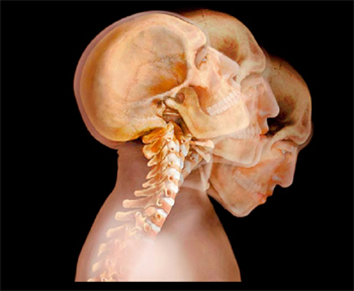

Problemas cervicales

Las cervicales están ligeramente curvadas hacia delante formando una lordosis y proporcionando gran flexibilidad y movilidad. El cuello soporta el peso de la cabeza y está contínuamente mandando impulsos nerviosos al cerebro: cada vez que movemos el cuerpo, la cabeza o los ojos también movemos unos grados los segmentos vertebrales cervicales. Esta coordinación fluida de